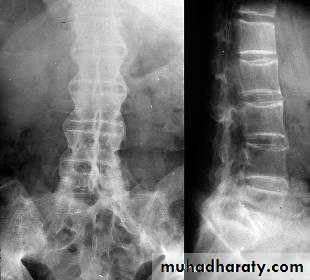

-X-rays:- The earliest radiological appearances in the spine are blurring of the upper or lower vertebral rims at the thoracolumbar junction(seen on lateral X-ray) caused by an enthesitis at the insertion of the intervertebral ligaments.

Sacroilitis, sclerosis, squaring of vertebrae, & bridging syndesmophytes ( marginal bony spurs that bridge the adjacent vertebral bodies) .

Bamboo spine